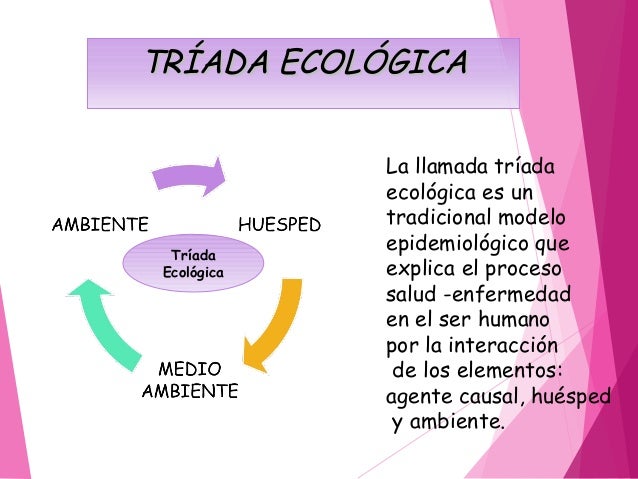

La triada ecológica: La Organización Panamericana de la salud (2011). La define como el modelo tradicional de la causalidad de las enfermedades transmisibles; en el cual la enfermedad será el resultado de la interacción entre el agente, el huésped susceptible y el ambiente.